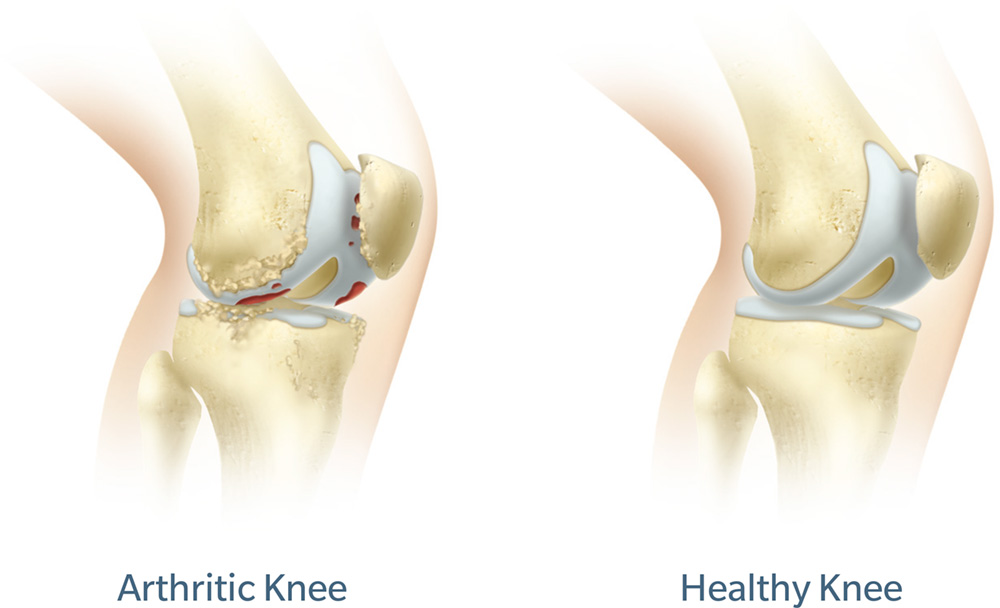

Arthritis in the knee joint

The knee is a hinge joint formed by the tibia (shinbone), femur (thighbone) and patella (kneecap). The ends of the bones in the knee joint are covered with cartilage, a tough, lubricating tissue that helps cushion the bones during movement.

Osteoarthritis, the most common form of arthritis, is a wear-and-tear condition that destroys joint cartilage and bone. It typically develops after years of constant motion and pressure in the joints. As the cartilage continues to wear away, the joint becomes increasingly painful and difficult to move. If conservative treatment options fail to provide relief, your surgeon may recommend total knee replacement using ROSA Knee robotic technology.